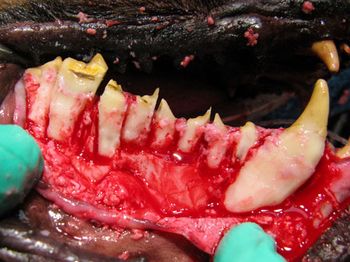

Extractions of teeth in dogs and cats are commonly categorized as simple or surgical, Surgical extractions involve periodontal flaps and the removal of bone to expose tooth roots. Simple extractions in some cases are not always simple as their name implies. Fractures during extraction may require surgical methods to complete the procedure.

Correct management of periodontal patients in veterinary practice demands a thorough understanding of veterinary dental radiographic anatomy, periodontal probing and many times open evaluation and direct visualization of diseased areas. Stage III periodontal disease in particular requires advanced skills and familiarization with periodontal pathophysiology to make decisions to attempt to grow new supportive tissue adjacent to compromised teeth or extract them.